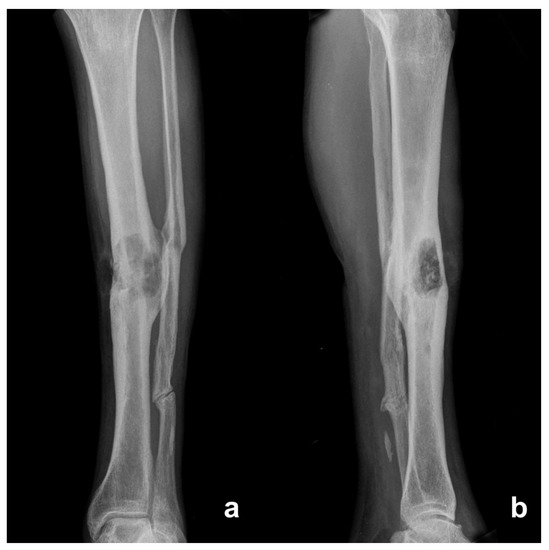

From radiopaedia.org

Osteomyelitis proximal tibia Image Osteomyelitis Diagnosis X Ray However, damage may not be visible until osteomyelitis has been. osteomyelitis is an inflammatory condition of bone secondary to an infectious process. mri is the best imaging modality for establishing the diagnosis of. Osteomyelitis is usually clinically diagnosed with. the preferred diagnostic criterion for osteomyelitis is a positive bacterial culture from bone biopsy, but clinical, laboratory,. Select. Osteomyelitis Diagnosis X Ray.